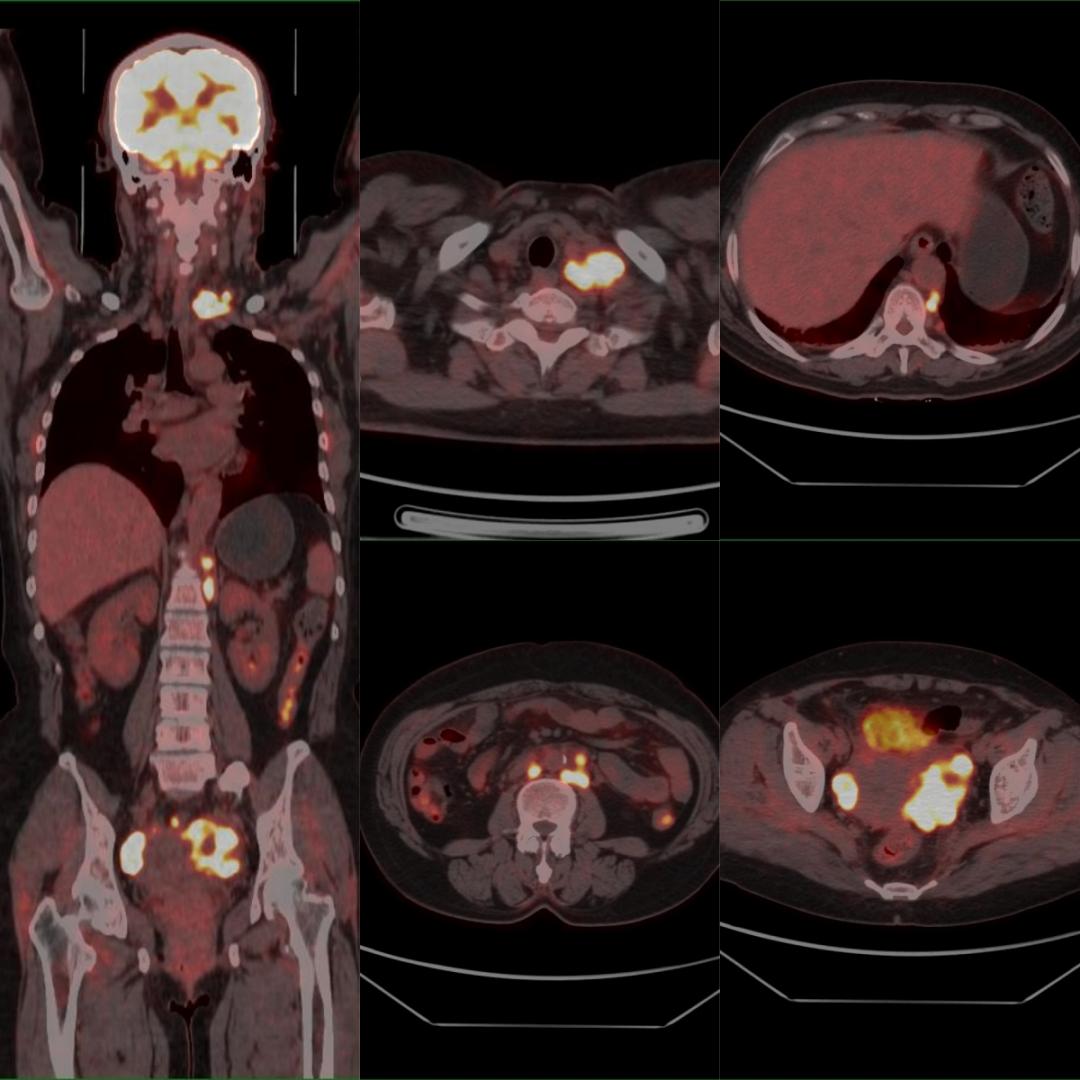

患者以“甲狀腺占位、左鎖骨上占位”入院,行超聲引導(dǎo)下左鎖骨上窩腫物穿刺術(shù),病理:考慮分化差的癌,結(jié)合免疫組化結(jié)果,考慮轉(zhuǎn)移的腺癌,建議檢查乳腺、肺等部位。為明確腫瘤原發(fā)灶,行PET/CT檢查,示:雙側(cè)卵巢、盆腔、腹膜后、后縱隔、左側(cè)鎖骨上多發(fā)高代謝病灶,診斷為雙側(cè)卵巢癌伴多發(fā)淋巴結(jié)轉(zhuǎn)移,后行手術(shù)、化療等治療。

雙側(cè)卵巢Ca伴多發(fā)淋巴結(jié)轉(zhuǎn)移

PET/CT用于卵巢癌淋巴結(jié)轉(zhuǎn)移的術(shù)前評估,其敏感度為83.3%,特異度為98.2%,準(zhǔn)確率為95.6%。因此可作為卵巢癌術(shù)前評估淋巴結(jié)轉(zhuǎn)移的重要方法。

本例患者初步診斷左側(cè)鎖骨上淋巴結(jié)不明來源轉(zhuǎn)移癌,臨床選擇PET/CT來尋找原發(fā)灶。PET/CT發(fā)現(xiàn)了非預(yù)期的原發(fā)灶(左側(cè)鎖骨上淋巴結(jié)轉(zhuǎn)移癌最常見的原發(fā)腫瘤并非卵巢,且初步病理提示排查乳腺和肺),大幅縮短了篩查原發(fā)灶的時(shí)間,減少了非針對性的檢查,節(jié)約了寶貴的資金,患者得到及時(shí)、科學(xué)的治療,獲益明顯。